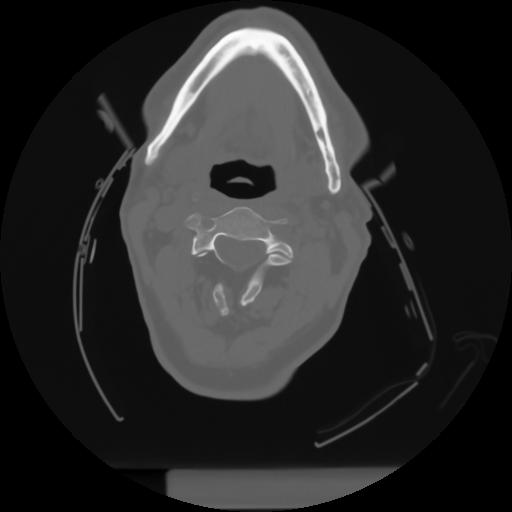

10 P.BLANDAS,,Axial,2.0,P.BLANDAS,,